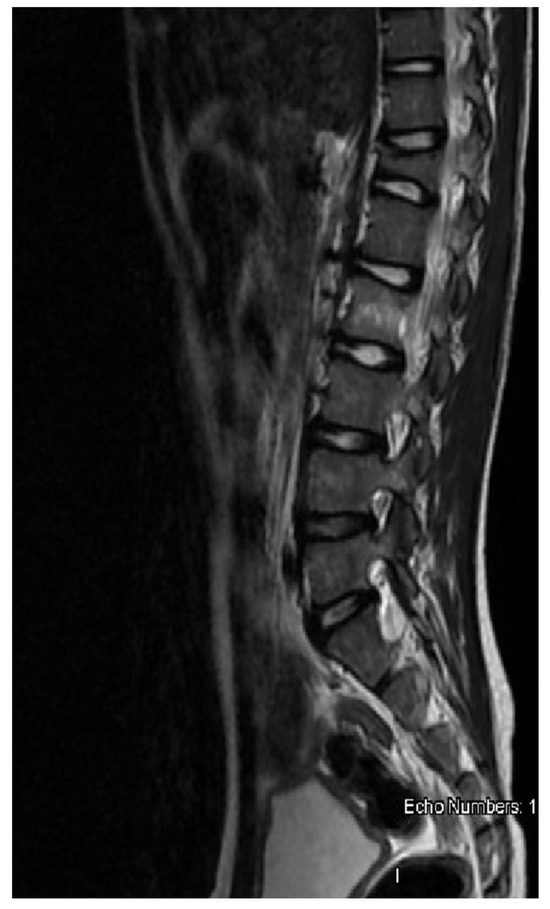

A previously healthy 9-year-old boy came to our attention for back pain, lasting more than 2 months, with no other symptoms; he had been treated with physiotherapy and anti-inflammatory drugs. On clinical examination, the boy was well-appearing, complaining of moderate back pain at the lumbar level. Complete blood count, lactate dehydrogenase, uric acid, C-reactive protein, and erythrocyte sedimentation rate were in the normal range. Spine magnetic resonance imaging (MRI) showed a signal alteration at the D12-L2 level (with a wedge-shaped D12 body) characterized by hypointensity at T1-weighted and hyperintensity at T2-weighted sequences; furthermore, an abnormal tissue involving medullary canal and neural foramina was appreciated at the D11-L1 level (Figure 1). Cerebral, thorax, and abdominal CT were of normal appearance. The boy underwent an open biopsy, and the histological diagnosis was ALCL, CD30+, ALK+, EMA+, perforin+, associated with numerous histiocytes CD68PGM1+. Positron emission tomography/computed tomography (PET-CT) showed high fluorodeoxyglucose (FDG) uptake at D11-L2 level, with spinal cord involvement. Lumbar puncture revealed the presence of 66 T-lymphoblasts/μL in the cerebrospinal fluid (CSF) and bone marrow aspirate was positive for NPM-ALK transcript, detected by qualitative RT-PCR. The patient was treated with six courses of chemotherapy according to the AIEOP LNH-97 protocol for ALCL, high-risk group, with CNS involvement (Table 1) [3]. MRD in bone marrow and peripheral blood was negative just after the first course of chemotherapy. PET-CT, performed after the second chemotherapy block, showed a complete metabolic response, confirmed also at the end of treatment. Spine MRI performed 2 weeks after stop-therapy demonstrated complete disappearance of both D12-L1 lesions and tissue proliferation in the D11-L1 region, with the persistence of mild signal alteration, without any contrast enhancement, at the L2 level only (Figure 2). During the follow-up, the boy was also monitored by the analysis of MRD in peripheral blood every month for the first three months, then every two months up to one year from the stop-therapy: NPM-ALK transcript was never detected. The patient is in clinical, radiological, and molecular remission at 12 months after the end of treatment.

Figure 2. Spine MRI after treatment: complete disappearance of both D12 lesion and tissue proliferation with persistence of mild signal alteration at L2 level.